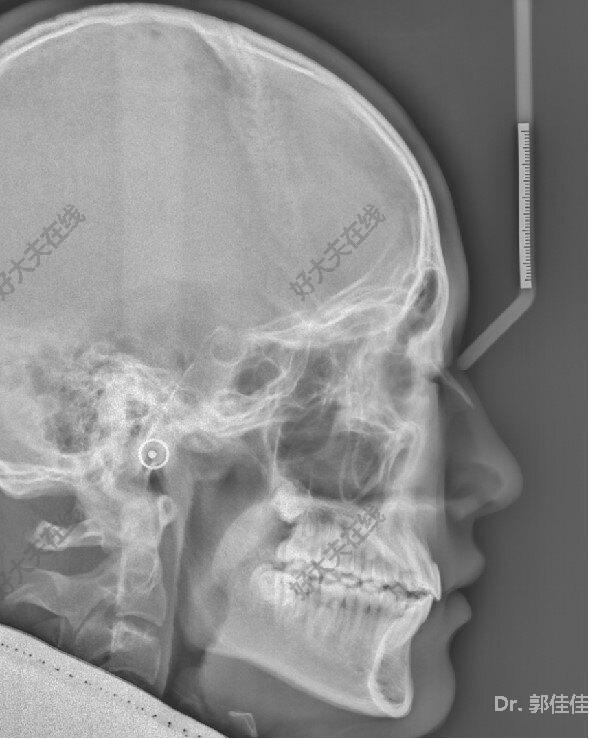

治疗前

11岁小男孩,主诉龅牙,牙齿不整齐。

检查:侧貌突,开唇露齿。上颌前突,下颌后缩,上前牙前突10mm左右,咬合深,咬至上颌粘膜,上下牙弓狭窄,牙列拥挤不齐。